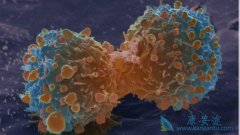

前列腺癌一直是男性肿瘤头号杀手,由于现代人生活的不规律,和工作的繁忙导致越来越多的人患上了前列腺癌,并且没有得到很好的医治,导致发现时前列腺癌细胞已经开始扩散,为了针对这种情况, 海外医疗 研究人员近日开发了一组复杂的分析工具对患有转移 ...

癌症作为当今世界上最难治愈的疾病,让人们谈癌色变,如果癌症是在早期被发现那么将很好治疗,几乎不会影响我们的生活,但由于现在的人们疏于检查导致许多人癌症被发现时就已经是中晚期,癌细胞已经开始扩散到其他部位。这也是超过90%癌症死亡的重要原因 ...